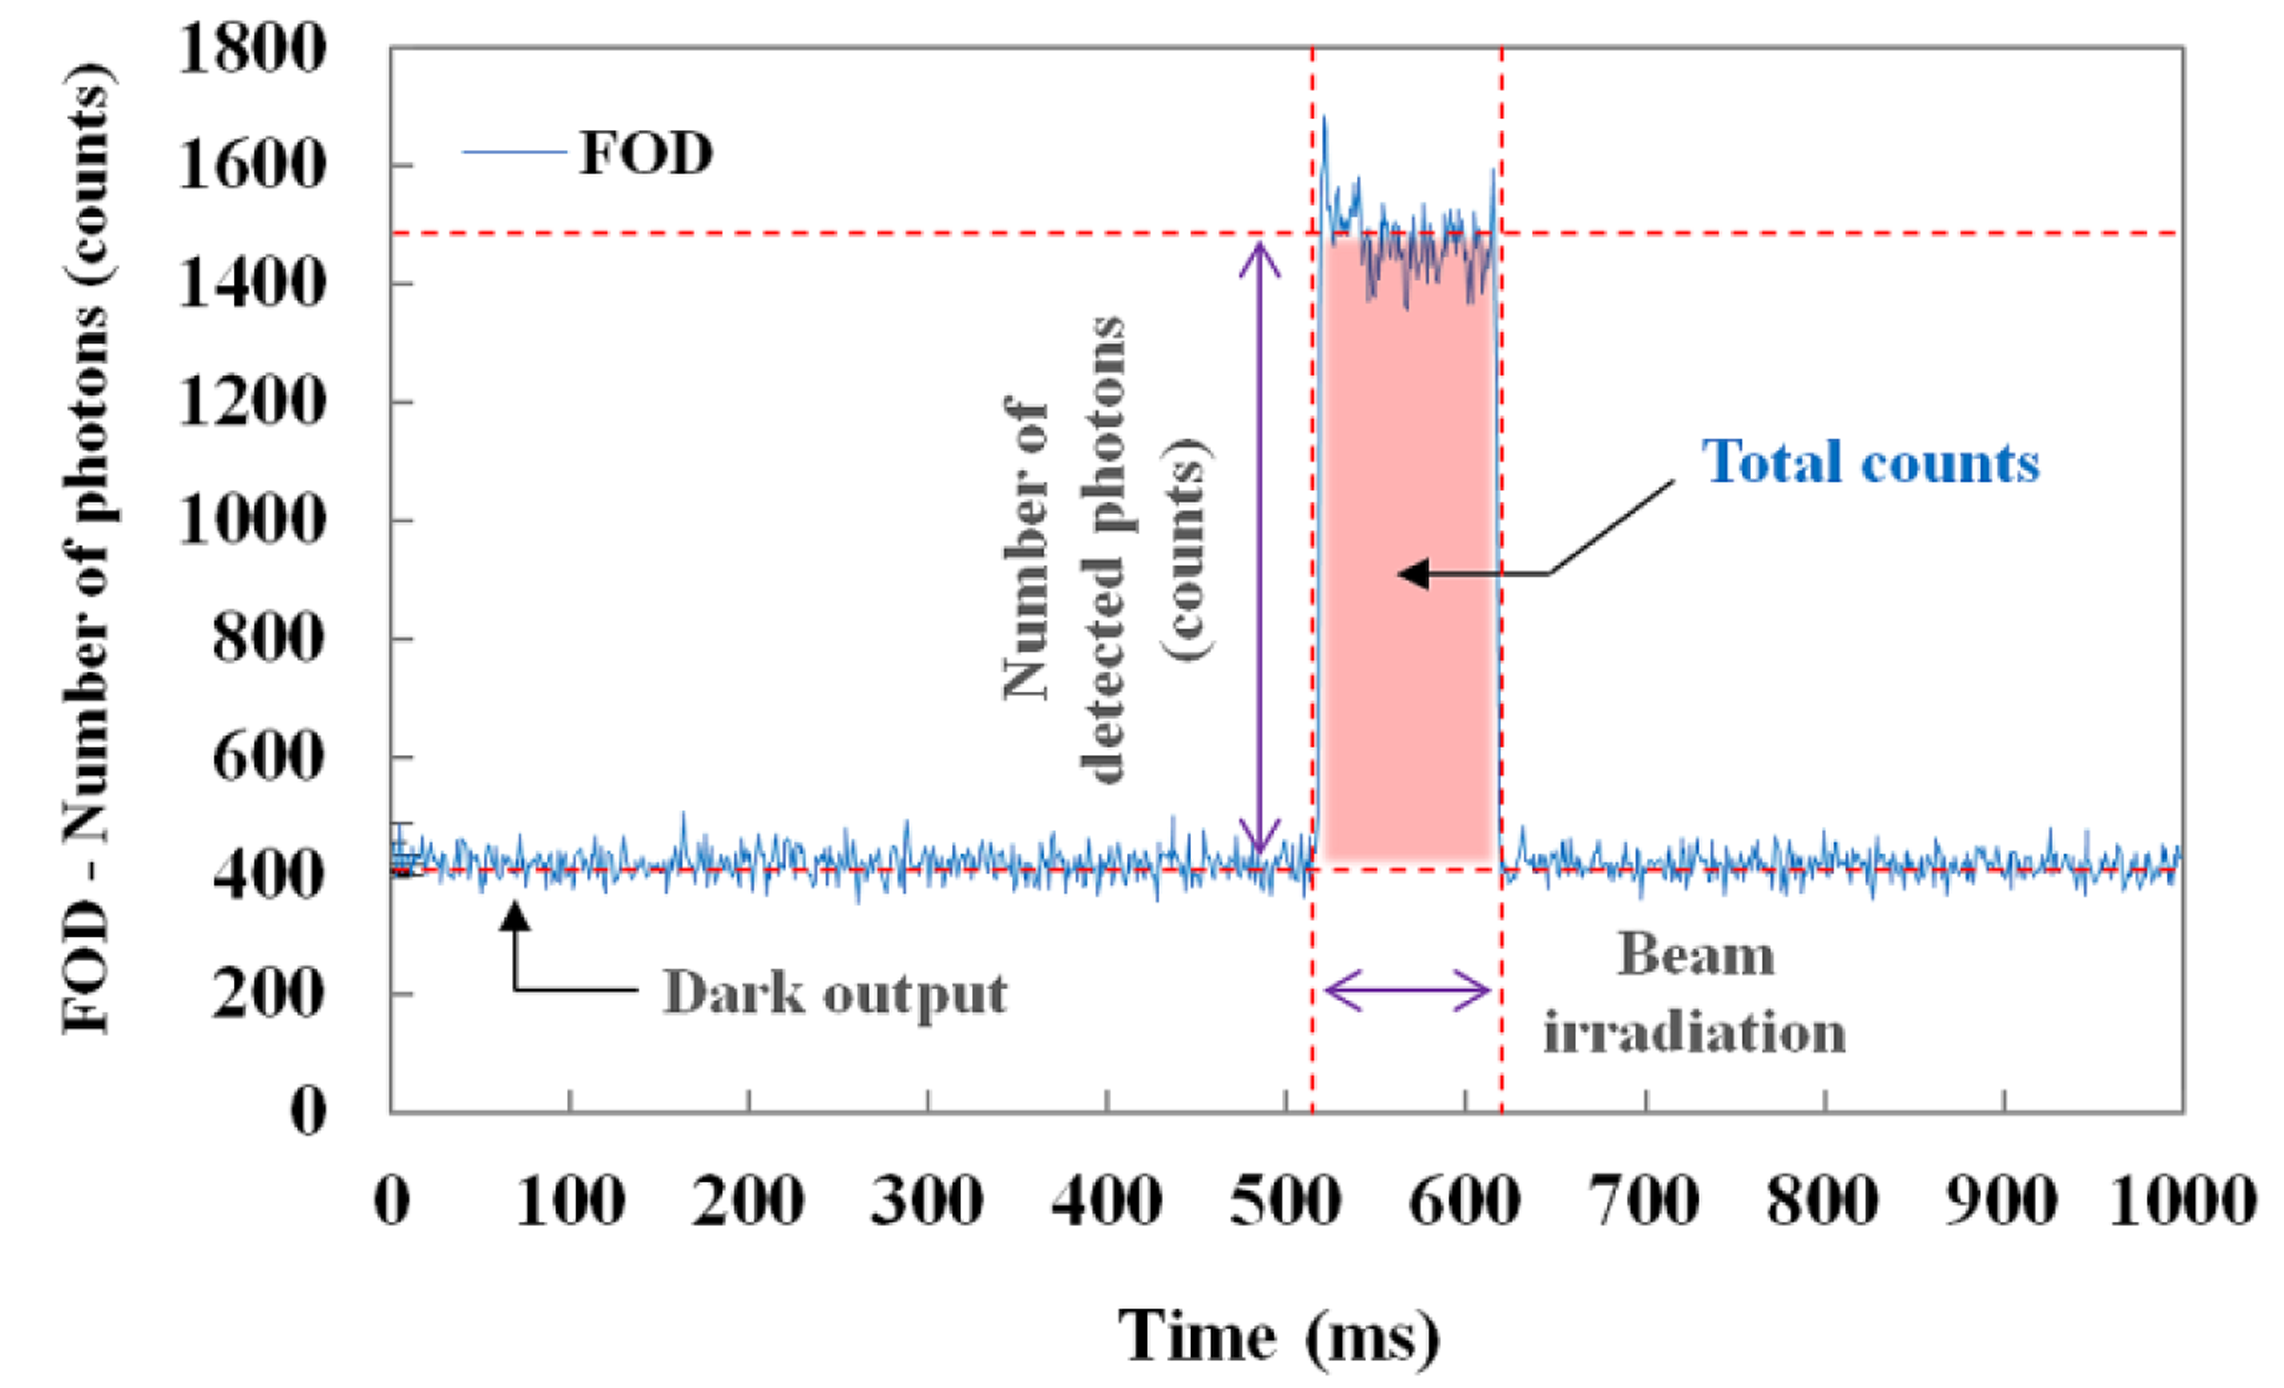

Figure 3 illustrates the raw data of real-time output signals from the MPPC module with a threshold level of 0.5 p.e. and a gate time of 1 ms. When the sensing probe was irradiated with an X-ray beam, we measured the number of detected scintillation photons (i.e., counts) in real time and also obtained the total counts of the scintillating light generated from the sensing probe during beam irradiation, as shown in Figure 3.

Through random and repeated experiments to improve accuracy, we measured the scintillating light in order to obtain the dose value, which changed with variations of the exposure parameters, such as the tube potential (kVp), current-time product (mAs), and focus-to-surface distance (FSD) or focus-to-image receptor (i.e., the flat panel detector of the DR system) distance (FID). The scintillation output signals of the FOD were then compared with the dose values simultaneously obtained using the SCD. For this experiment, the values of the tube potential, current-time product (tube current × irradiation time), FSD, and field size were fixed at 100 kVp, 5 mAs (50 mA × 100 ms), 85 cm, and 30 × 30 cm2, respectively. During X-ray irradiation, the SCD was placed alongside the sensing probe of the FOD. Error bars were drawn on all data points in the figures showing the experimental results; however, most error bars were within the data points because they were too small to be displayed.